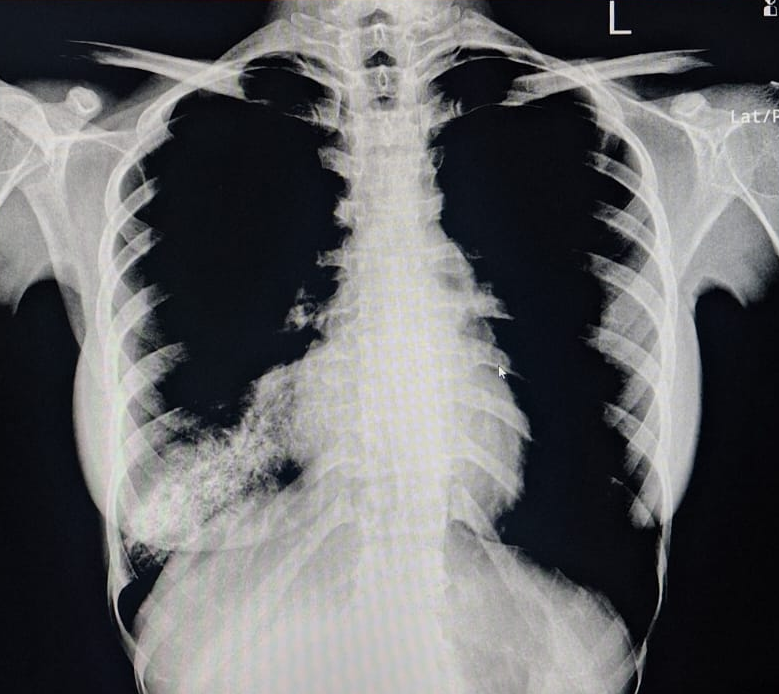

A young 23 year old female first presented in 2015 with complaints of right-sided chest pain and swelling. A thorough clinico-radiological evaluation was done and general surgeon consultation sought. Imaging revealed an expansile lytic lesion of the right 9th rib (Fig 1). Other long bone x-ray evaluation was done and found no abnormalities. We planned for excision biopsy of 9th rib and patient underwent surgical excision (Fig 2). Histopathological examination confirmed a benign intraosseous hemangioma(Fig 3). Post-operative recovery was uneventful. 6 monthly followed by yearly radiological follow-up was being done till pre-covid period. Patient lost to follow-up during 2020-2022 Covid-19 period.

• 2015: Expansile lytic lesion of right 9th rib with cortical thinning (Fig 1).